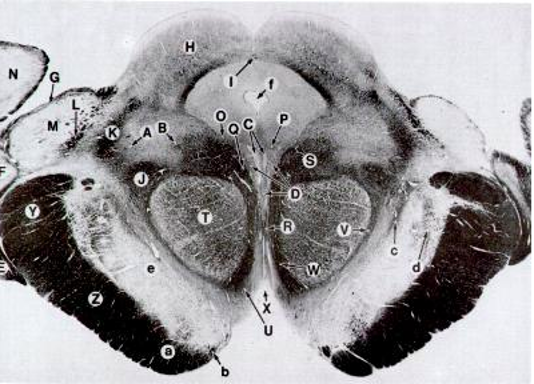

Rostral Midbrain Cross section

<p>Z</p>

Z

Corticospinal Tract

<p>T</p>

T

Red Nucleus

<p>H</p>

H

Superior Colliculi

<p>D</p>

D

CrN. III Nucleus

<p>C</p>

C

<p>e</p>

e

Substancia Nigra

<p>f</p>

f

Cerebral Aquaduct